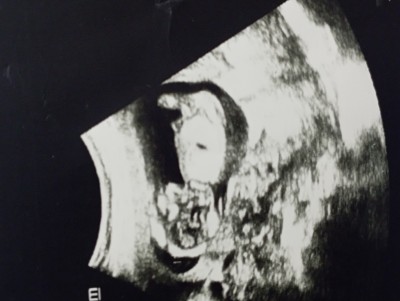

Tipi kıza benziyor hissiyatım da kız :)

Bende hamileyim benim kızımın tipine benziyor karşılaştırdım :)

Attım benim udrasona kim baksa kesin kız demişlerdi bu resimde belli değildi doktor biraz daha bekleyelim demişti ortadaki pozda nubu çok belli nuba bakarak 100 de 100 kız demişlerdi Bana öylr de çıktı 16 haftada da öğrendim tam cinsiyeti

Ben erkek hissediyorum

Sanki ortadaki şeyi pipiye benzettim

En üstteki görüntü  benziyor özellikle kafa yapısı image